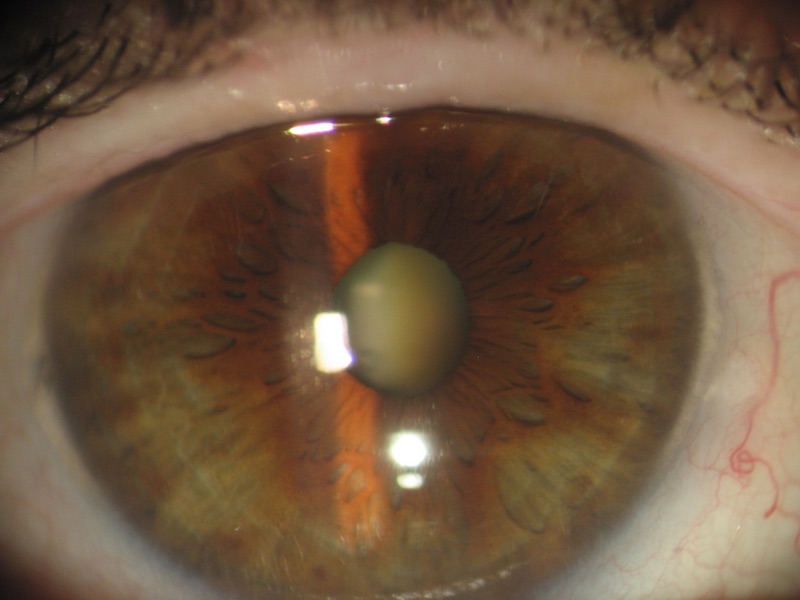

1) Cataract ++

Despite an important cataract with an invisible fundus of eye in Volk 90Δ or indirect ophthalmoscopy, Eidon manages to see the fundus of the eye.

Malgré une importante cataracte avec un fond d'oeil invisible en Volk 90∆ ou en ophtalmoscopie indirecte, Eidon arrive à apercevoir le fond d'oeil.

Nonostante significativa cataratta con un fondo invisibile in Volk 90Δ o oftalmoscopia indiretta, Eidon riesce a vedere il fondo.

- Cataract ++

- Cataract++